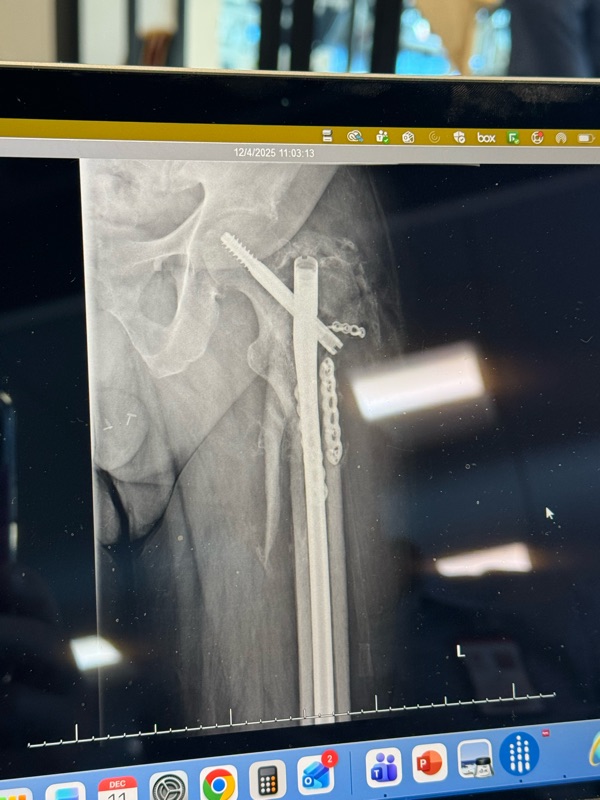

Oh! My hip is not healing very fast. It has one month to shape up and heal properly or I am going under the knife or saw etc. I was making great progress, then just stalled and there was an increase in pain. If I do go into surgery it is not a minor thing. As I get close to the 1 month mark I will write more. Below is the problem area minus the porn